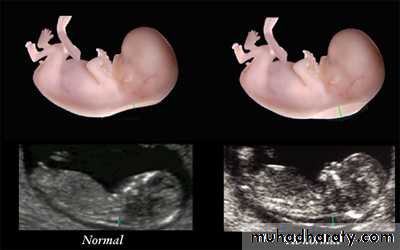

Spina bifida:’lemon’&’banana’sign